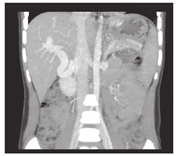

搭桥后血流通畅情况,搭桥前门静脉的平均压力33 cmH2O (26~45 cmH2O),搭桥后门静脉压力下降至18.7 cmH2O(14~24 cmH2O)。肝脏膨胀,脾脏背膜皱缩,游离创面渗血减少。静脉造影显示,分流后肝内门静脉右支及其分支灌注显影,达到肝脏实质边缘。患儿随访6个月至1.5年,超声及增强CT显示所有患儿的搭桥分流血管开放通畅,门静脉海绵变消失,肝体积增大(图3、图4),无消化道出血复发,脾功能亢进症状消失,血小板、白细胞和血红蛋白在正常水平。上消化道造影显示食管静脉曲张明显减轻。